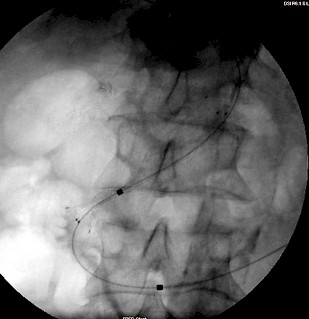

Die Offenhaltung der beiden Hepaticusäste sowie des DHC kann sowohl mittels Plastikprothesen, als auch mittels der metallischen Endoprothesen (Stents) erreicht werden. Dabei ist die Offenheitsrate der metallischen Stents gegenüber den Plastikprothesen überlegen (d. h. sie bleiben länger offen und benötigen weniger Re-Eingriffe). Gecoverte (mit einer Plastikmembran bedeckte) Metallstents sind wiederum hinsichtlich der Offenheitsrate den unbeschichteten Metallstents überlegen. Neben technischen Problemen (höhere Perforationsgefahr von selbstexplantierenden Stents, hohe Dislokationsrate von gecoverten Stentgrafts aus dem DHC in den Darm, schwierigere Intervention bei Verschluss eines Metallstents, höheres Risiko bei nachfolgenden Operationen wenn elektrisch eine Blutstillung erfolgen soll) auch Kostenprobleme.

Falls nur der ableitende Gallengang (DHC) stenosiert und versorgt werden muss, kann dieser über den Zugangsweg der PTC/PTCD mittels eines selbstexpandierbaren Stent dauerhaft versorgt werden. Liegt dagegen ein (tumorös bedingter) Verschluss nicht nur des DHC, sondern auch der beiden Hepaticusäste vor (und damit ein Problem des Gallenabfluß aus beiden Leberlappen) sollte eine beidseitige PTC/PTCD erfolgen. Anschließend sollte mittels zweier (parallel über beide Gallengänge bis in den DHC vorgeschobener) Stents eine "Rekonstruktion" der Hepatikusgabel und Schienung des gemeinsamen DHC versucht werden. Ein alleiniges Stenten nur des einen Hepaticusastes (meist von rechts, da der rechte Leberlappen größer als der linke ist) kommt nur in Frage, wenn das erwartete Überleben des Patienten sehr kurz und die linke Leber sehr klein ist. Von beidseits eingebrachte Stents verbessern das Überleben gegenüber nur einem einseitigen Stent

Fallbeispiel:

Patient mit Pankreaskopf-Ca, Leber- und Lungenmetastasen und Tumorverschluß des Gallengangs: